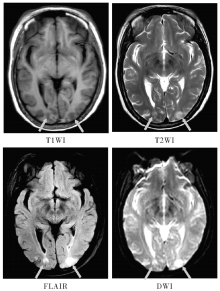

随着全球范围内自身免疫性疾病发病率的不断上升,系统性红斑狼疮(systemic lupus erythematosus, SLE)作为一种典型的自身免疫性疾病,其导致的脑损害日益受到关注。SLE患者脑损害发病率高且预后不良,而早期准确识别脑损害对及时干预和治疗至关重要。磁共振成像技术作为一种非侵入性影像学检查方法,可提供多模态、高分辨率的丰富数据,在SLE早期脑损害的定量研究和临床诊断评估中具有重要应用价值。本文旨在探讨多模态磁共振技术在SLE早期脑损害的机制研究和临床应用中的意义,以期为SLE患者脑损害的早期干预和治疗提供更有力的支持。

YANG Yifan, ZHANG Guofang, XU Jian. Application of multimodal magnetic resonance in identification of early brain damage in systemic lupus erythematosus[J]. Journal of Internal Medicine Concepts & Practice, 2024, 19(06): 372-378.